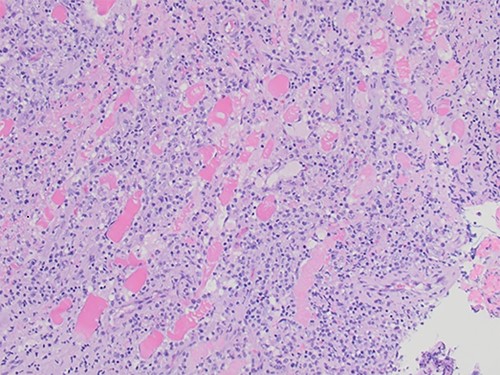

An excisional biopsy was performed 4 days after the initial biopsy, revealing skeletal muscle with a histiocytic/monocytic infiltrate with marked necrosis, and a lymph node demonstrating sinus histiocytosis (Fig. 2). Microscopic examination demonstrated a polymorphous inflammatory infiltrate within skeletal muscle and soft tissue. The infiltrate was predominantly composed of histiocytes and monocytes with scattered lymphocytes and neutrophils. Large regions of coagulative necrosis were present. A few large histiocytes showed atypical morphologic features such as vesicular chromatin and prominent nucleoli. However, upon immunohistochemical analysis, the cells did not express aberrant markers and showed a low proliferative index.

Skeletal muscle with a dense inflammatory infiltrate of predominantly histiocytes and monocytes (H&E, ×20 objective).